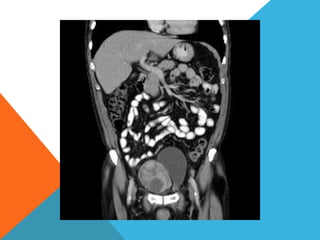

El paciente presentó síntomas de sangrado digestivo y pérdida de peso. Exámenes revelaron gastritis crónica asociada a H. pylori. Un tumor fue descubierto en una colonoscopia normal. La cirugía removió un tumor fibroide solitario, una rara neoplasia mesenquimal que usualmente crece lento y tiene bajo potencial de malignidad. El pronóstico después de la remoción quirúrgica es generalmente bueno.